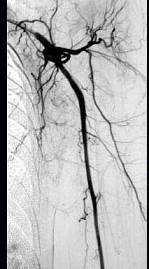

问题 43岁女性患者,突发左手疼痛伴多个指头麻木就诊,行左上肢动脉照影,示左侧桡动脉广泛的充盈缺损,结合临床考虑左侧桡动脉病变为 ( )

选项 A、桡动脉血栓形成 B、桡动脉假性动脉瘤 C、桡动脉炎 D、桡动脉真性动脉瘤 E、桡动脉夹层

答案 A